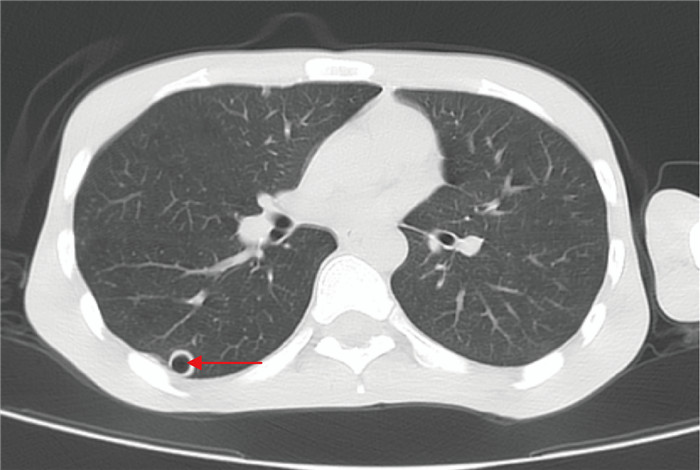

诊疗过程如下。3月24日,患者到院后查血常规示白细胞计数20.62×109/L↑,中性粒细胞百分比93.1%↑;C反应蛋白23.86 mg/L↑;降钙素原0.488 ng/mL↑;脑脊液测压大于320 mmH2O。脑脊液常规示白细胞335.2×106/L↑,潘氏试验2+;脑脊液生化示氯108.0 mmoL/L↓,葡萄糖 < 1.11 mmoL/L↓,脑脊液蛋白4 056.97 mg/L↑。头胸计算机断层扫描(computed tomography, CT)提示:1.考虑双肺弥漫性细支气管炎;左肺上叶尖后段、右肺下叶背段薄壁空洞,真菌性感染待排,请结合临床;2.脑室系统扩张,右侧顶叶皮层下片状低密度灶;3.左肺上叶散在钙化灶(见图 1~2)。3月25日晨经验用药予哌拉西林/他唑巴坦4.5 g q8h和莫西沙星0.4 g qd,16: 56脑脊液涂片结果显示:抗酸+ +(抗酸染色结果如图 3)。根据抗酸染色结果,临床医师立即予异烟肼片600 mg qd,利福平0.6 g qd,吡嗪酰胺片0.5 g qd,盐酸乙酰丁醇片0.75 g qd四联抗结核治疗。经过治疗,患者生命体征相对稳定,意识状态仍较淡漠,3月29日转至专科医院继续抗结核治疗。

| 图 1 患者胸部CT征象 Fig. 1 Chest CT signs of the patient |

|